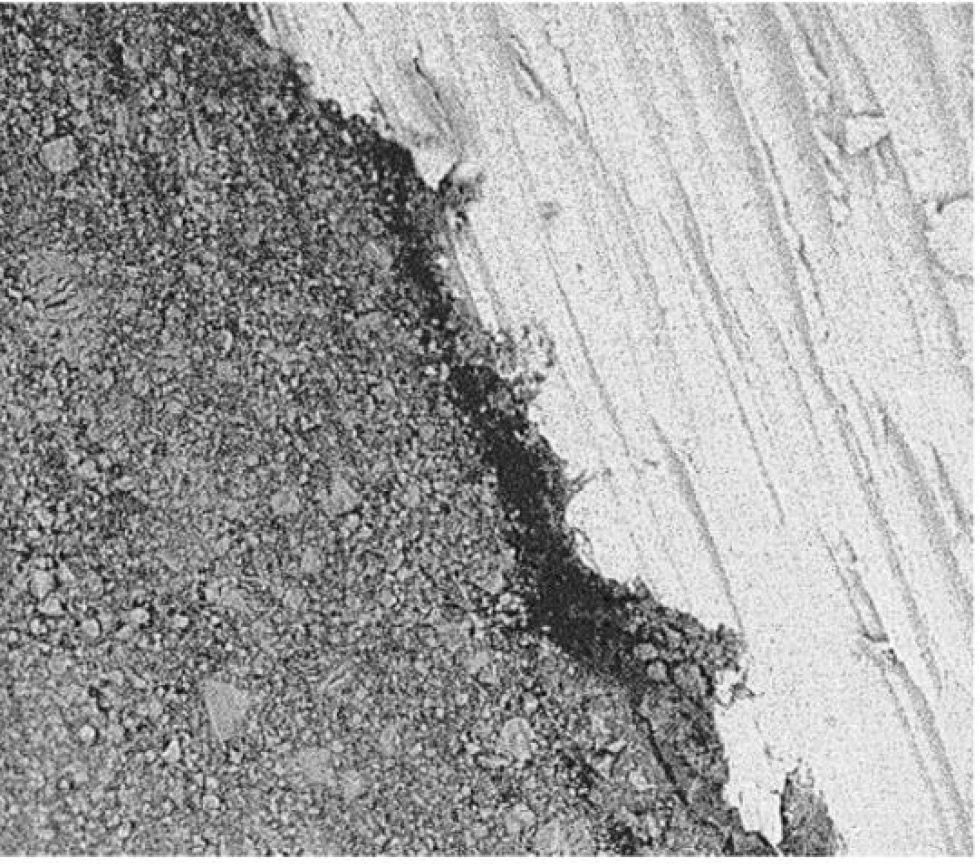

In the second study group, 60% had violations of the marginal fit of the restoration. On the electron diffraction pattern, at the border of the restoration, inclusions (Fig. 6) from microbrush fibers were observed. We hypothesize that the Prime&Bond Universal adhesive system (Dentsply) affected the fibers and caused them to fall out of the plastic rod.

A significant additional result of the study is the identification of brush fibers on the electron diffraction pattern, which is the basis for recommending the use of brushes for applying adhesive instead of brushes.